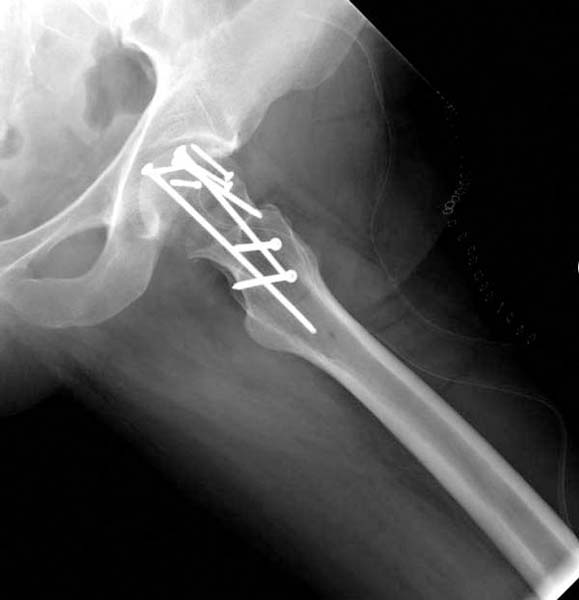

> стабильная.. На третьий день провели стабилизацию перелома бедра

> антеградным остеосинтезом.

> Закрытый БИОС решает множественные проблемы связанные с лечением

> переломов, но проблема дистальной блокировки без рентгена до сих пор

> остается нерешенной. Рекламированные производителями приспособления для

> дистальной блокировки из-за различной кривизны кости не эффективны или

> стоит очень дорого (Smith&Nephew SureLock). Задержка операции из-за

> блокировки не всегда удовлетворяет, и многих вынуждает искать